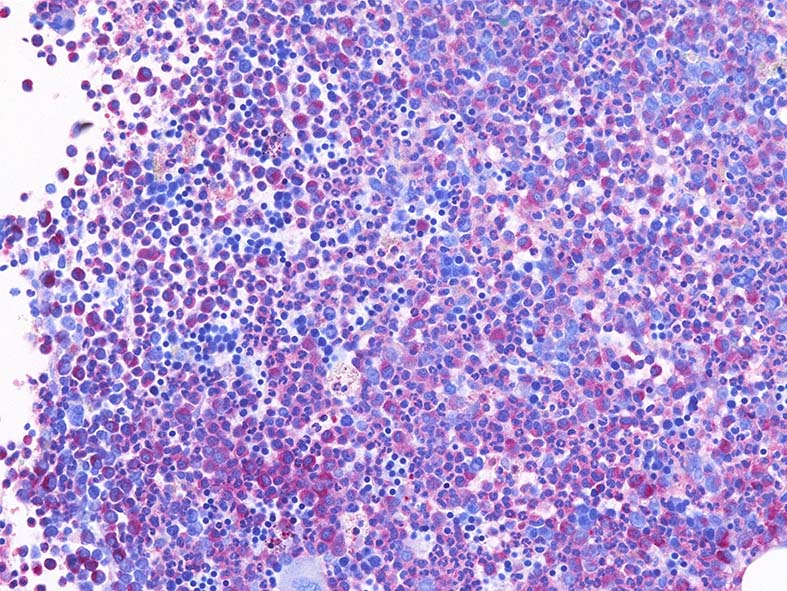

Naphtohl-ASD-CAE Fig.01

Fig.01: hypercellular marrow. ASDで赤染する細胞の増加=granulopoietic hyperplasiaがある.

Fig.02: 幼若な顆粒球が増加している. 赤芽球は散在しており血島は不明瞭である. 過形成髄なのにFig.02に成熟大型巨核球はみられない.

Fig.03: granulopoietic hyperplasia. 成熟顆粒球の増加もある.